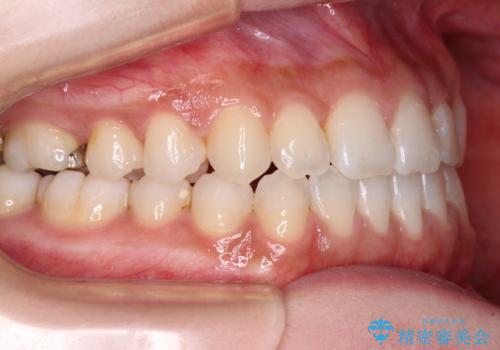

舌突出癖で口元が開いてしまう 舌トレーニングを行ったインビザライン矯正

- 前歯の上下スペースと前歯の隙間を気にして来院された患者様です。

インビザラインにより上下の前歯の隙間を閉じていくこととしました。

上下の隙間に舌が入り込むことが、すきっ歯やオープンバイトの原因であったため、舌の筋肉のトレーニングも並行して行い、後戻りの抑制を図りました。